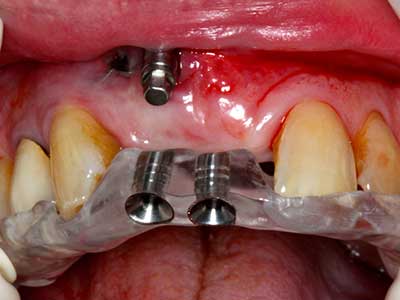

Indicazione: incisione ossea

Il tessuto osseo non è semplicemente una struttura minerale, ma contiene anche una percentuale significativa di fibre di collagene. Ciò significa che non possiede solo una buona forza di compressione, ma anche un certo livello di flessibilità che è possibile sfruttare durante l'esecuzione degli accrescimenti di osso. Nella procedura di espansione classica con incisione ossea, la cresta alveolare atrofizzata viene incisa longitudinalmente ed espansa con cautela dopo aver raggiunto una profondità di osteotomia adeguata (figg. 13-16), idealmente senza una sostanziale rimozione del periostio (Brugnami, Caiazzo et al. 2014, Stricker, Fleiner et al. 2014). I sistemi a piastra e vite con distanza di espansione incrementale si sono dimostrati efficaci nella separazione delle due lamelle ossee restando al di sotto della soglia di frattura. In generale, sono richieste larghezze dell'osso residuo di almeno 3-4 mm (Chiapasco, Zaniboni et al. 2006) per garantire un'adeguata flessibilità e una copertura sufficiente dell'osso per gli impianti futuri. Se necessario, un'osteotomia di rilascio verticale su uno o più lati può migliorare la flessibilità. Una combinazione con ulteriori tecniche di accrescimento, in particolare dal lato buccale, è stata descritta come un'alternativa alla tecnica classica.

La procedura di incisione è particolarmente atraumatica e non comporta una perdita significativa di dimensione durante l'utilizzo delle seghe piezoelettriche, così come non si notano differenze rilevanti tra impianti in mandibole incise e impianti in una cresta alveolare senza deficit osseo (Chiapasco, Zaniboni et al. 2006, Danza, Guidi et al. 2009). Una sufficiente irrigazione continua è essenziale, tuttavia, in particolare con incisione profonda e localmente ristretta, per prevenire la sollecitazione termica nelle regioni apicali dell'osteotomia.